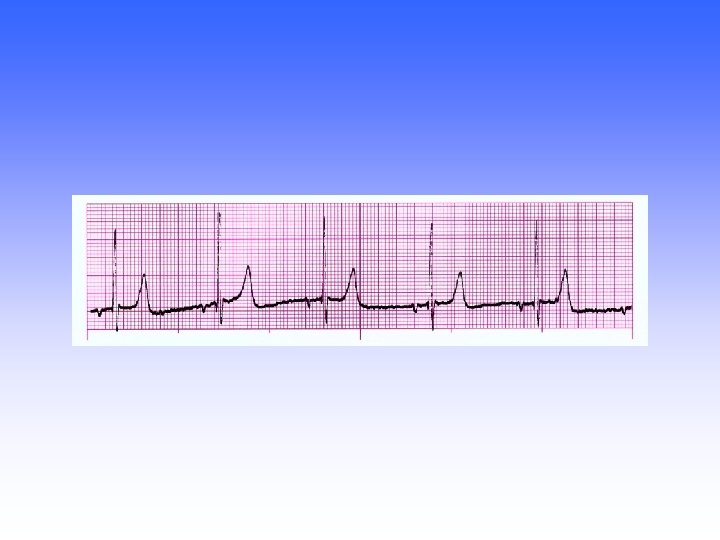

A-V Sequential Pacemaker at 75 Regular: regular P-wave: PACER SPIKE PRI: NA (~0. 20

A-V Sequential Pacemaker at 75 Regular: regular P-wave: PACER SPIKE PRI: NA (~0. 20 sec) QRS: PACER SPIKE